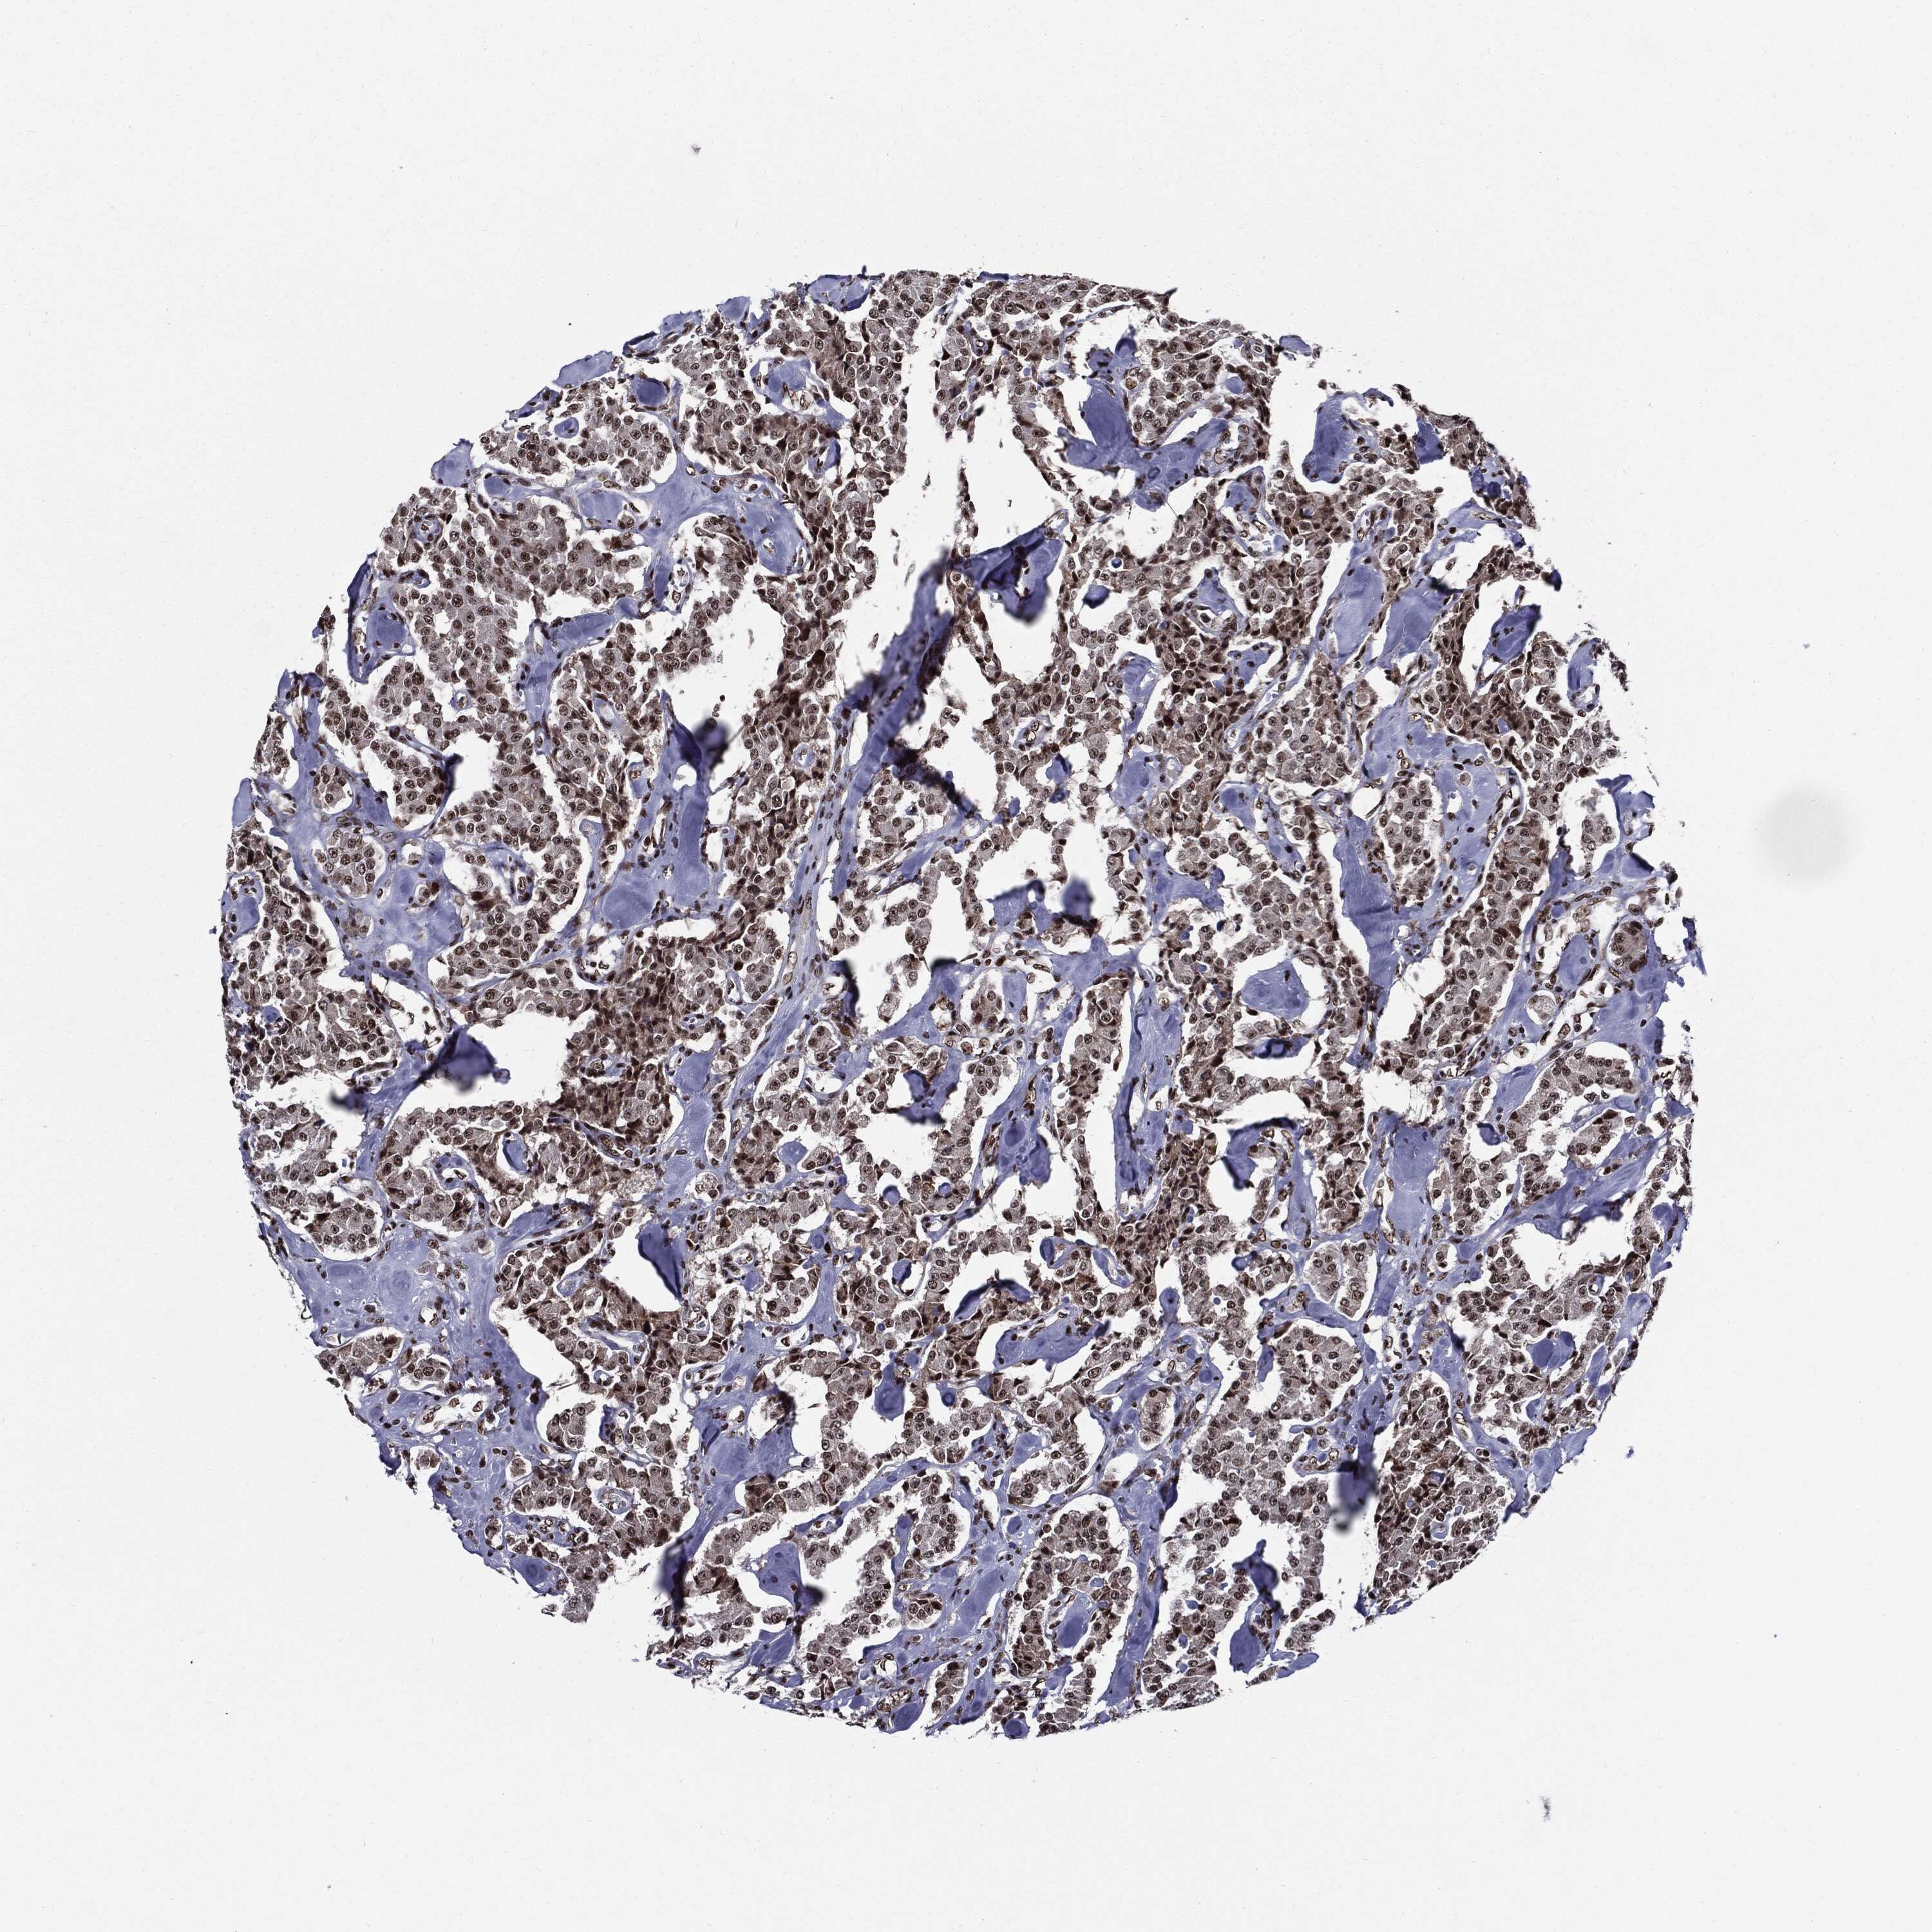

CARCINOID - Protein expressioni

A mouse-over function shows sample information and annotation data. Click on an image to view it in a full screen mode. Samples can be filtered based on level of antibody staining by selecting one or several of the following categories: high, medium, low and not detected. The assay and annotation is described here.

Antibody stainingi

Antibody staining in the annotated cell types in the current human tissue is reported as not detected, low, medium, or high, based on conventional immunohistochemistry profiling in selected tissues. This score is based on the combination of the staining intensity and fraction of stained cells.

Each image is clickable and will lead to virtual microscopy that enables deeper exploration of all samples and also displays staining intensity scores, fraction scores and subcellular localization as well as patient and tissue information for each sample.

Antibody HPA024037

Antibody HPA065325

Antibody HPA074591

Antibody CAB025417

Staining

High

Medium

Low

Not detected

Intensity

Strong

Moderate

Weak

Negative

Quantity

>75%

75%-25%

<25%

None

Location

Nuclear

Cytoplasmic/membranous

Cytoplasmic/membranous,nuclear

Carcinoid, malignant, NOS

Carcinoma, NOS